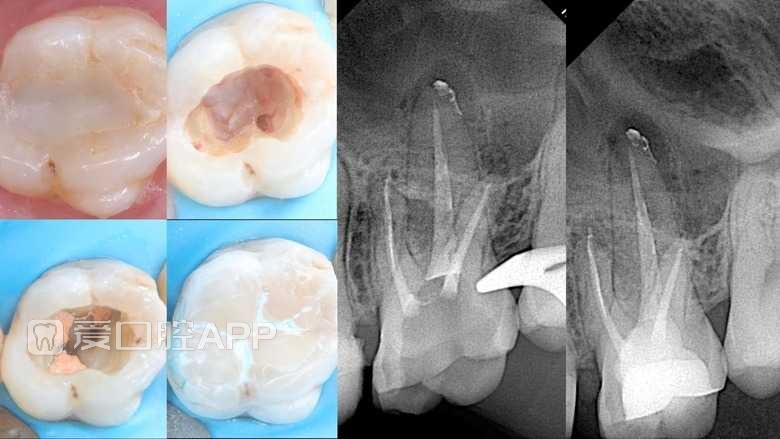

看个根充 —— 下6

by Hassan Eladl